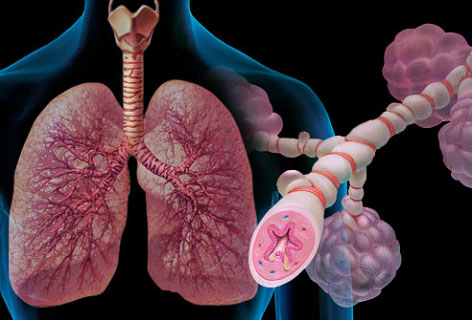

Ερευνα: Οι πνεύμονες των καπνιστών επανέρχονται «μαγικά» εάν κόψουν το κάπνισμα

Οι πνεύμονες έχουν μια σχεδόν «μαγική» ικανότητα να επιδιορθώνουν τις καρκινικές μεταλλάξεις που προκαλεί το κάπνισμα, αρκεί κανείς να το κόψει, σύμφωνα με μια νέα ελπιδοφόρα βρετανική επιστημονική έρευνα